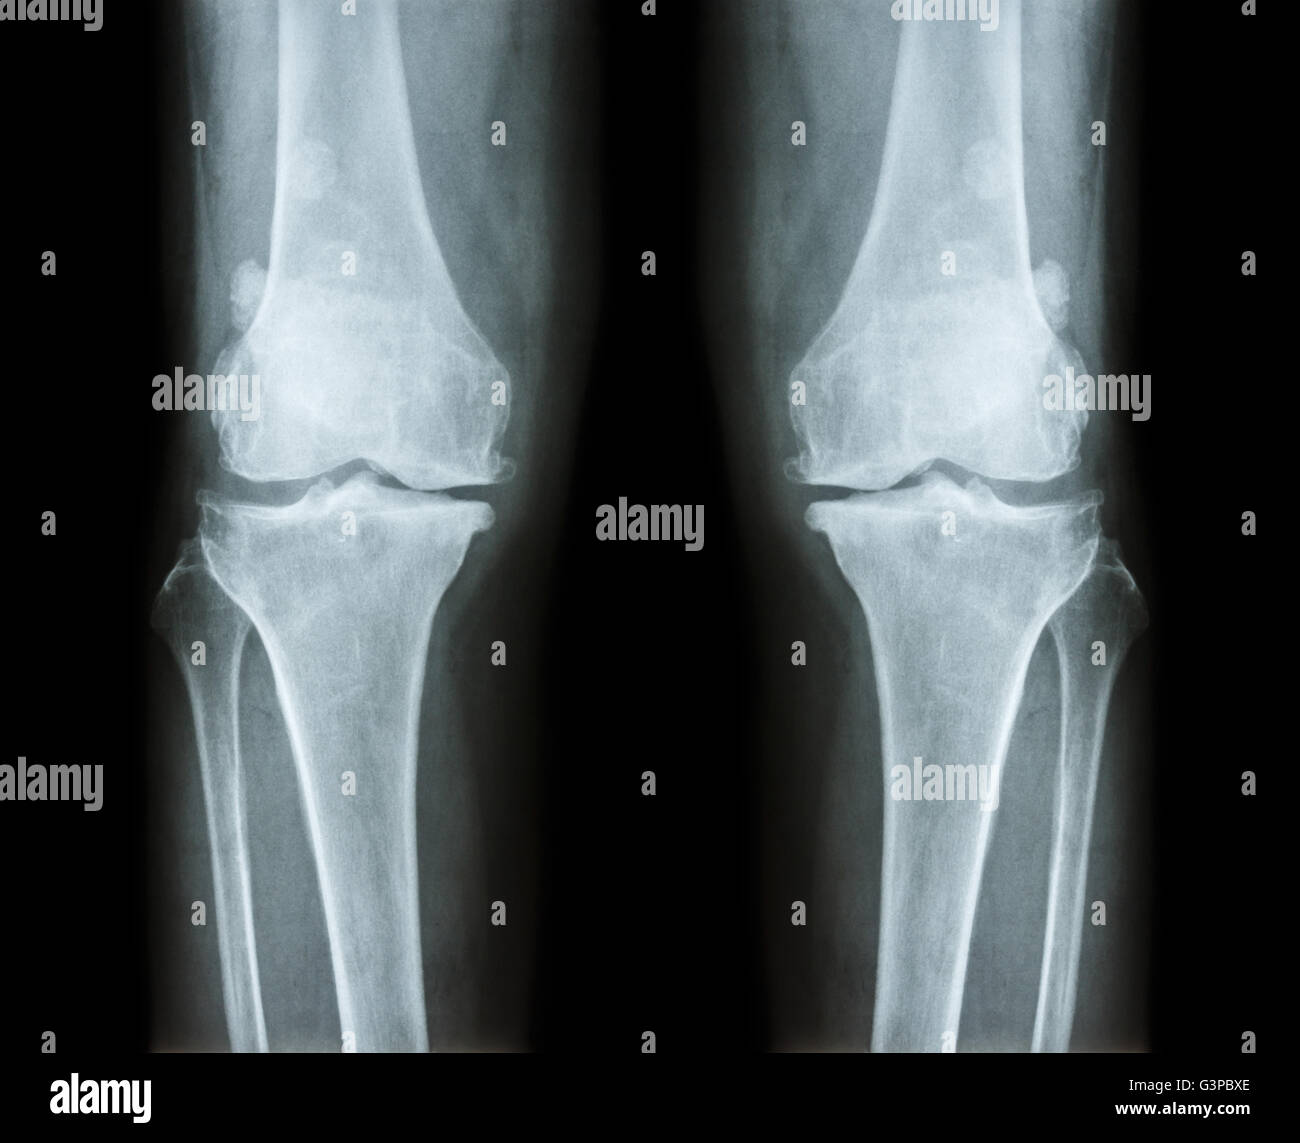

L'arthrose du genou les . film x-ray ( AP ) postérieure antérieure - de montrer l'espace étroit du genou mixte , ( ) , épi ostéophyte subco Banque D'Imageshttps://www.alamyimages.fr/image-license-details/?v=1https://www.alamyimages.fr/photo-image-l-arthrose-du-genou-les-film-x-ray-ap-posterieure-anterieure-de-montrer-l-espace-etroit-du-genou-mixte-epi-osteophyte-subco-105598478.html

L'arthrose du genou les . film x-ray ( AP ) postérieure antérieure - de montrer l'espace étroit du genou mixte , ( ) , épi ostéophyte subco Banque D'Imageshttps://www.alamyimages.fr/image-license-details/?v=1https://www.alamyimages.fr/photo-image-l-arthrose-du-genou-les-film-x-ray-ap-posterieure-anterieure-de-montrer-l-espace-etroit-du-genou-mixte-epi-osteophyte-subco-105598478.htmlRFG3PBX6–L'arthrose du genou les . film x-ray ( AP ) postérieure antérieure - de montrer l'espace étroit du genou mixte , ( ) , épi ostéophyte subco

L'arthrose du genou les . film x-ray ( AP ) postérieure antérieure - de montrer l'espace étroit du genou mixte , ( ) , épi ostéophyte subco Banque D'Imageshttps://www.alamyimages.fr/image-license-details/?v=1https://www.alamyimages.fr/photo-image-l-arthrose-du-genou-les-film-x-ray-ap-posterieure-anterieure-de-montrer-l-espace-etroit-du-genou-mixte-epi-osteophyte-subco-105598486.html

L'arthrose du genou les . film x-ray ( AP ) postérieure antérieure - de montrer l'espace étroit du genou mixte , ( ) , épi ostéophyte subco Banque D'Imageshttps://www.alamyimages.fr/image-license-details/?v=1https://www.alamyimages.fr/photo-image-l-arthrose-du-genou-les-film-x-ray-ap-posterieure-anterieure-de-montrer-l-espace-etroit-du-genou-mixte-epi-osteophyte-subco-105598486.htmlRFG3PBXE–L'arthrose du genou les . film x-ray ( AP ) postérieure antérieure - de montrer l'espace étroit du genou mixte , ( ) , épi ostéophyte subco

L'arthrose du genou les . film x-ray ( AP ) postérieure antérieure - de montrer l'espace étroit du genou mixte , ( ) , épi ostéophyte subco Banque D'Imageshttps://www.alamyimages.fr/image-license-details/?v=1https://www.alamyimages.fr/photo-image-l-arthrose-du-genou-les-film-x-ray-ap-posterieure-anterieure-de-montrer-l-espace-etroit-du-genou-mixte-epi-osteophyte-subco-105598501.html

L'arthrose du genou les . film x-ray ( AP ) postérieure antérieure - de montrer l'espace étroit du genou mixte , ( ) , épi ostéophyte subco Banque D'Imageshttps://www.alamyimages.fr/image-license-details/?v=1https://www.alamyimages.fr/photo-image-l-arthrose-du-genou-les-film-x-ray-ap-posterieure-anterieure-de-montrer-l-espace-etroit-du-genou-mixte-epi-osteophyte-subco-105598501.htmlRFG3PBY1–L'arthrose du genou les . film x-ray ( AP ) postérieure antérieure - de montrer l'espace étroit du genou mixte , ( ) , épi ostéophyte subco

L'arthrose du genou les . film x-ray ( AP ) postérieure antérieure - de montrer l'espace étroit du genou mixte , ( ) , épi ostéophyte subco Banque D'Imageshttps://www.alamyimages.fr/image-license-details/?v=1https://www.alamyimages.fr/photo-image-l-arthrose-du-genou-les-film-x-ray-ap-posterieure-anterieure-de-montrer-l-espace-etroit-du-genou-mixte-epi-osteophyte-subco-105598460.html

L'arthrose du genou les . film x-ray ( AP ) postérieure antérieure - de montrer l'espace étroit du genou mixte , ( ) , épi ostéophyte subco Banque D'Imageshttps://www.alamyimages.fr/image-license-details/?v=1https://www.alamyimages.fr/photo-image-l-arthrose-du-genou-les-film-x-ray-ap-posterieure-anterieure-de-montrer-l-espace-etroit-du-genou-mixte-epi-osteophyte-subco-105598460.htmlRFG3PBWG–L'arthrose du genou les . film x-ray ( AP ) postérieure antérieure - de montrer l'espace étroit du genou mixte , ( ) , épi ostéophyte subco

L'ARTHROSE DU GENOU Arthrose du genou ( ). Film x-ray deux genou ( vue avant ) show spatial commun étroit ( perte de cartilage ) , osteophy Banque D'Imageshttps://www.alamyimages.fr/image-license-details/?v=1https://www.alamyimages.fr/photo-image-l-arthrose-du-genou-arthrose-du-genou-film-x-ray-deux-genou-vue-avant-show-spatial-commun-etroit-perte-de-cartilage-osteophy-87802628.html

L'ARTHROSE DU GENOU Arthrose du genou ( ). Film x-ray deux genou ( vue avant ) show spatial commun étroit ( perte de cartilage ) , osteophy Banque D'Imageshttps://www.alamyimages.fr/image-license-details/?v=1https://www.alamyimages.fr/photo-image-l-arthrose-du-genou-arthrose-du-genou-film-x-ray-deux-genou-vue-avant-show-spatial-commun-etroit-perte-de-cartilage-osteophy-87802628.htmlRFF2RN44–L'ARTHROSE DU GENOU Arthrose du genou ( ). Film x-ray deux genou ( vue avant ) show spatial commun étroit ( perte de cartilage ) , osteophy

L'ARTHROSE DU GENOU Arthrose du genou ( ). Film x-ray deux genou ( vue avant ) show spatial commun étroit ( perte de cartilage ) , osteophy Banque D'Imageshttps://www.alamyimages.fr/image-license-details/?v=1https://www.alamyimages.fr/photo-image-l-arthrose-du-genou-arthrose-du-genou-film-x-ray-deux-genou-vue-avant-show-spatial-commun-etroit-perte-de-cartilage-osteophy-87802655.html

L'ARTHROSE DU GENOU Arthrose du genou ( ). Film x-ray deux genou ( vue avant ) show spatial commun étroit ( perte de cartilage ) , osteophy Banque D'Imageshttps://www.alamyimages.fr/image-license-details/?v=1https://www.alamyimages.fr/photo-image-l-arthrose-du-genou-arthrose-du-genou-film-x-ray-deux-genou-vue-avant-show-spatial-commun-etroit-perte-de-cartilage-osteophy-87802655.htmlRFF2RN53–L'ARTHROSE DU GENOU Arthrose du genou ( ). Film x-ray deux genou ( vue avant ) show spatial commun étroit ( perte de cartilage ) , osteophy

L'ARTHROSE DU GENOU Arthrose du genou ( ). Film x-ray deux genou ( vue avant ) show spatial commun étroit ( perte de cartilage ) , osteophy Banque D'Imageshttps://www.alamyimages.fr/image-license-details/?v=1https://www.alamyimages.fr/photo-image-l-arthrose-du-genou-arthrose-du-genou-film-x-ray-deux-genou-vue-avant-show-spatial-commun-etroit-perte-de-cartilage-osteophy-87802612.html

L'ARTHROSE DU GENOU Arthrose du genou ( ). Film x-ray deux genou ( vue avant ) show spatial commun étroit ( perte de cartilage ) , osteophy Banque D'Imageshttps://www.alamyimages.fr/image-license-details/?v=1https://www.alamyimages.fr/photo-image-l-arthrose-du-genou-arthrose-du-genou-film-x-ray-deux-genou-vue-avant-show-spatial-commun-etroit-perte-de-cartilage-osteophy-87802612.htmlRFF2RN3G–L'ARTHROSE DU GENOU Arthrose du genou ( ). Film x-ray deux genou ( vue avant ) show spatial commun étroit ( perte de cartilage ) , osteophy

L'ARTHROSE DU GENOU Arthrose du genou ( ). Film x-ray deux genou ( vue avant ) show spatial commun étroit ( perte de cartilage ) , osteophy Banque D'Imageshttps://www.alamyimages.fr/image-license-details/?v=1https://www.alamyimages.fr/photo-image-l-arthrose-du-genou-arthrose-du-genou-film-x-ray-deux-genou-vue-avant-show-spatial-commun-etroit-perte-de-cartilage-osteophy-87802643.html

L'ARTHROSE DU GENOU Arthrose du genou ( ). Film x-ray deux genou ( vue avant ) show spatial commun étroit ( perte de cartilage ) , osteophy Banque D'Imageshttps://www.alamyimages.fr/image-license-details/?v=1https://www.alamyimages.fr/photo-image-l-arthrose-du-genou-arthrose-du-genou-film-x-ray-deux-genou-vue-avant-show-spatial-commun-etroit-perte-de-cartilage-osteophy-87802643.htmlRFF2RN4K–L'ARTHROSE DU GENOU Arthrose du genou ( ). Film x-ray deux genou ( vue avant ) show spatial commun étroit ( perte de cartilage ) , osteophy